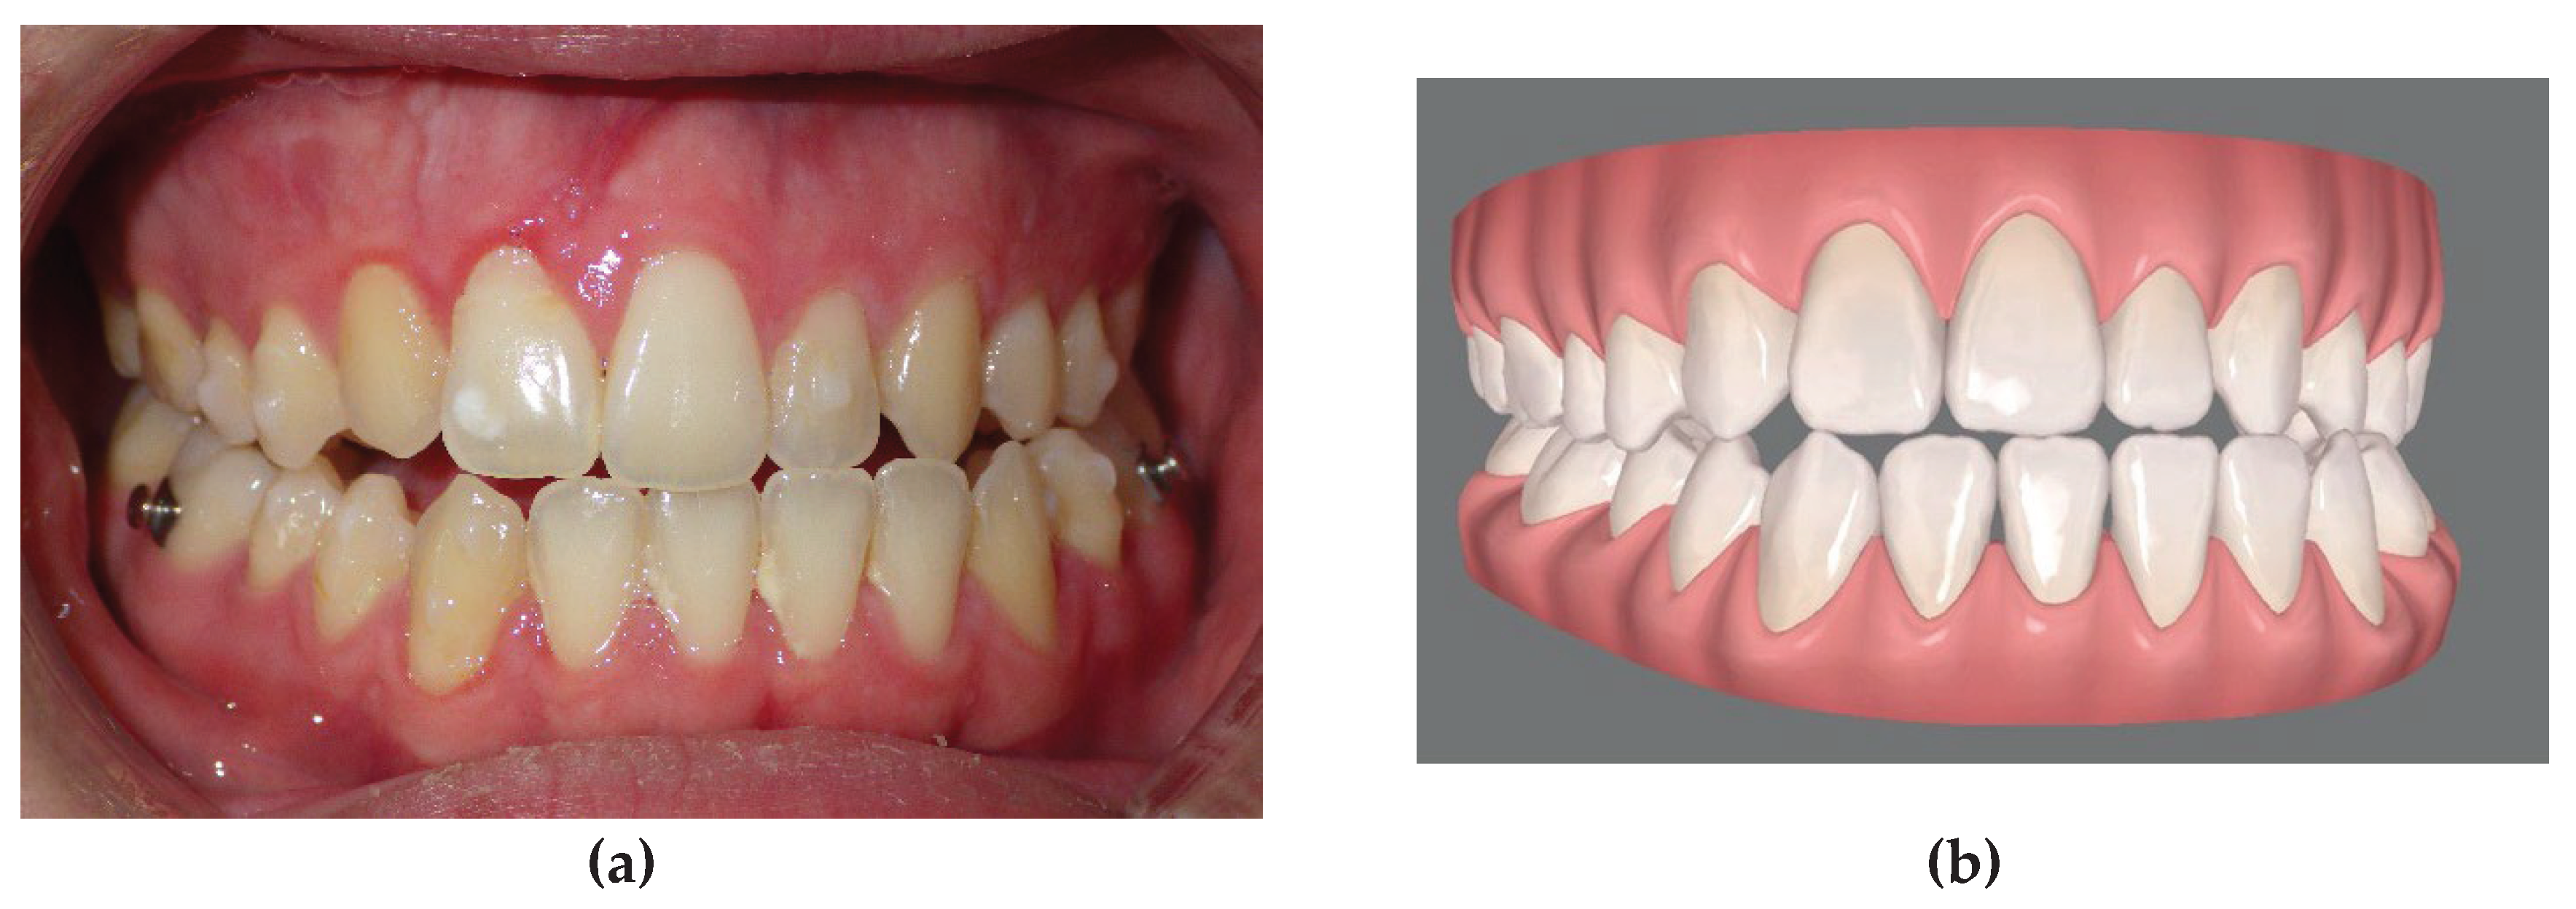

Figure 3. a, final occlusion obtained by clear aligner pre-surgical preparation. Note that the patient underwent an extraction of the left lower first premolar in order to avoid the mandibular osteotomy and allow the orthodontic decompensation; b, virtual simulation of the final occlusion elaborated with clin check software.

Pre surgical orthodontic treatment time was similar for the two techniques. The fixed appliance patients were treated for an average of 16.3 ± 4 months (range 9 – 22 months) (p > 0.05 n.s.), with an average of 10.2 ± 1.6 appointments (p<0.05). The Invisalign patients required an average of 18.4 ± 3 months (range 11 - 23) pre-surgically, with an average of 5.1 ± 0.8 appointments. The figures refer to a UCLP patient of the sample group treated with a two-piece Le Fort I osteotomy with a mandibular osteotomy. (Figure 5).